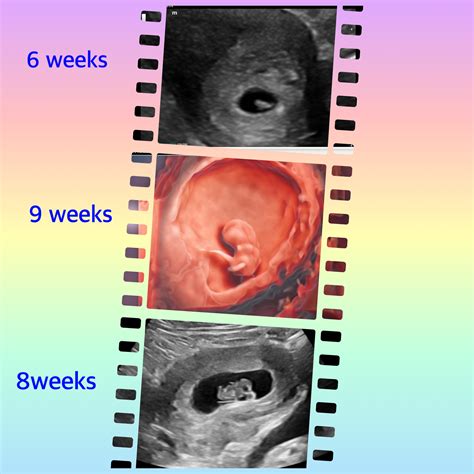

Embarking on the journey of parenthood is an exciting and transformative experience. One of the most anticipated milestones during pregnancy is the 6 week ultrasound. This early prenatal check-up provides valuable insights into the developing fetus and offers reassurance to expectant parents. Understanding the significance of the 6 week ultrasound and what to expect can help alleviate anxiety and prepare you for the journey ahead.

• Assessment of Gestational Age: The ultrasound helps determine the gestational age of the fetus, which is essential for monitoring growth and development throughout the pregnancy.

• 8 week ultrasound

• 6 week ultrasound fetal pole